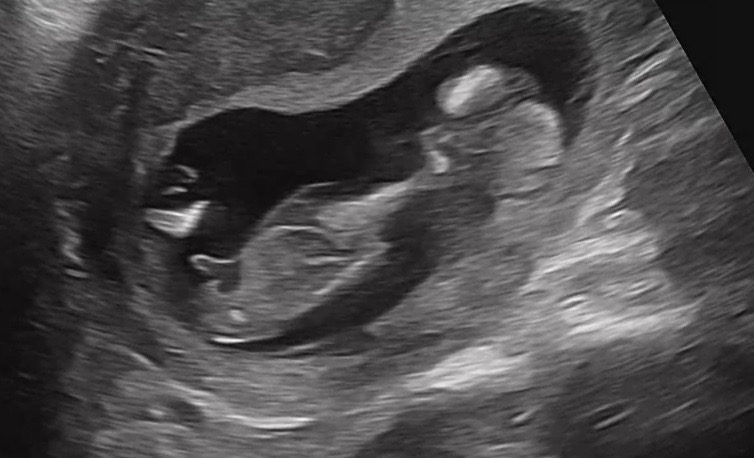

13주 성별 봐주실래요?

원장님은 고!츄!! 짧고 굵게 말씀하셨는데 빌리 AI로 넣었더니 딸 75%가 나와서 희망 품는 중입니다ㅠㅠ 고수님들 봐주세요ㅜㅜ